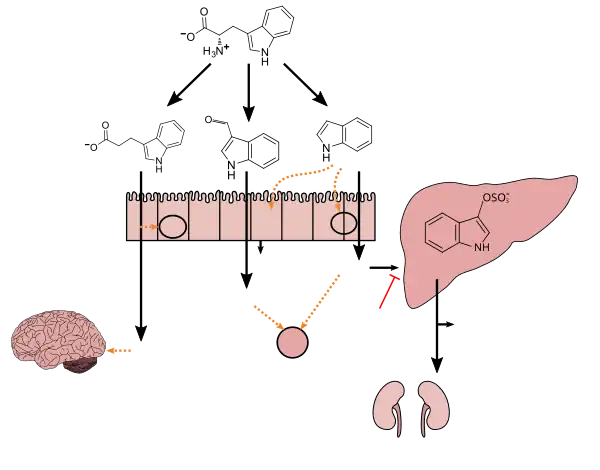

Tryptophan metabolism by human gut microbiota ()

|

- ^ a b c d e f g h i Zhang LS, Davies SS (April 2016). "Microbial metabolism of dietary components to bioactive metabolites: opportunities for new therapeutic interventions". Genome Med. 8 (1): 46. doi:10.1186/s13073-016-0296-x. PMC 4840492. PMID 27102537.

Lactobacillus spp. convert tryptophan to indole-3-aldehyde (I3A) through unidentified enzymes [125]. Clostridium sporogenes convert tryptophan to IPA [6], likely via a tryptophan deaminase. ... IPA also potently scavenges hydroxyl radicals

Table 2: Microbial metabolites: their synthesis, mechanisms of action, and effects on health and disease

Figure 1: Molecular mechanisms of action of indole and its metabolites on host physiology and disease - ^ Wikoff WR, Anfora AT, Liu J, et al. (March 2009). "Metabolomics analysis reveals large effects of gut microflora on mammalian blood metabolites". Proc. Natl. Acad. Sci. U.S.A. 106 (10): 3698–3703. Bibcode:2009PNAS..106.3698W. doi:10.1073/pnas.0812874106. PMC 2656143. PMID 19234110.

Production of IPA was shown to be completely dependent on the presence of gut microflora and could be established by colonization with the bacterium Clostridium sporogenes.

IPA metabolism diagram - ^ "3-Indolepropionic acid". Human Metabolome Database. University of Alberta. Retrieved 12 June 2018.